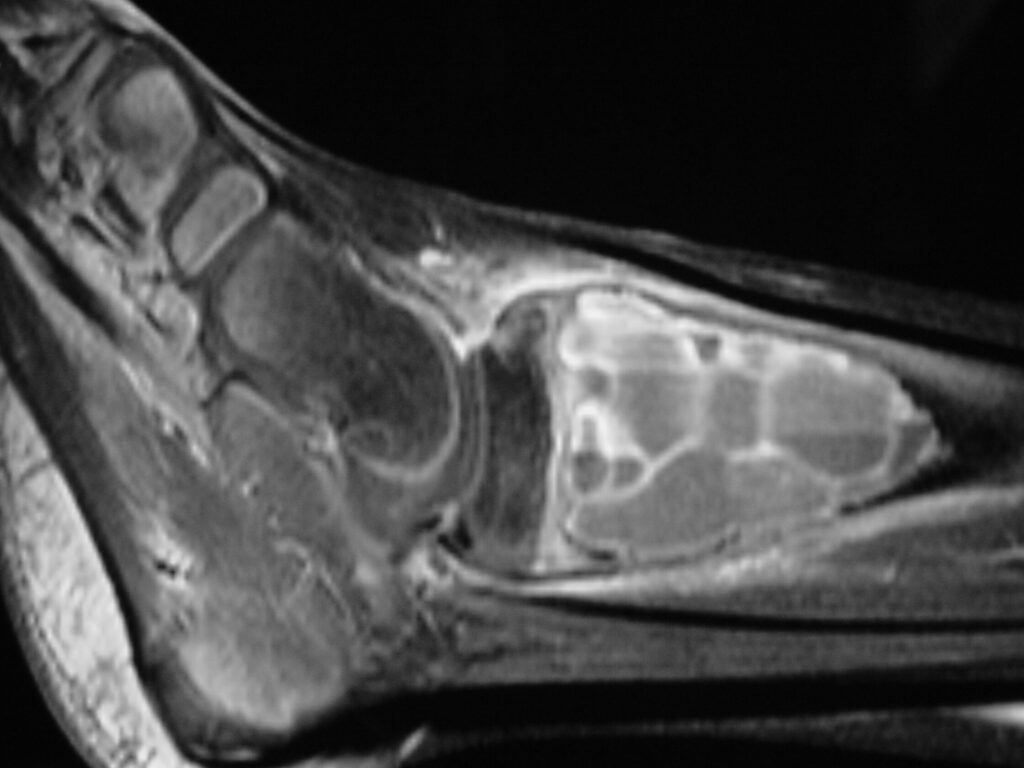

Fig 2 a-e. MRI of an ABC of Distal Tibia: Fig 2 a-c: geographic cystic expansile lesion with fluid-fluid levels. The fluid-fluid levels are caused by bleeding into the cavities. The blood collects and the degredation products settle to the gravity dependent areas of the cavities. This shows up as fluid-fluid levels on the MRI. Fig 2 d,e: This is a gadolinium enhanced MRI of the ABC of the distal tibia. There is peripheral and septal enhancement indication cyst formation. The contrast outlines the cystic cavities but does not enter into the center

Fig 2b: Sagittal T2 weighted MRI of and ABC

Fig 2d: Coronal gadolinium enhanced MRI of an ABC

Fig 2e: Sagittal gadolinium enhanced MRI of an ABC